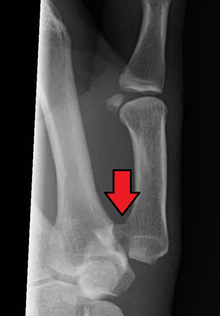

Bennett fracture on x-ray | |

Bennett fracture is a fracture of the base of the first metacarpal bone which extends into the carpometacarpal (CMC) joint.[1] This intra-articular fracture is the most common type of fracture of the thumb, and is nearly always accompanied by some degree of subluxation or frank dislocation of the carpometacarpal joint.

Though these fractures commonly appear quite subtle or even inconsequential on radiographs, they can result in severe long-term dysfunction of the hand if left untreated. In his original description of this type of fracture in 1882, Bennett stressed the need for early diagnosis and treatment in order to prevent loss of function of the thumb CMC joint, which is critical to the overall function of the hand.[3]